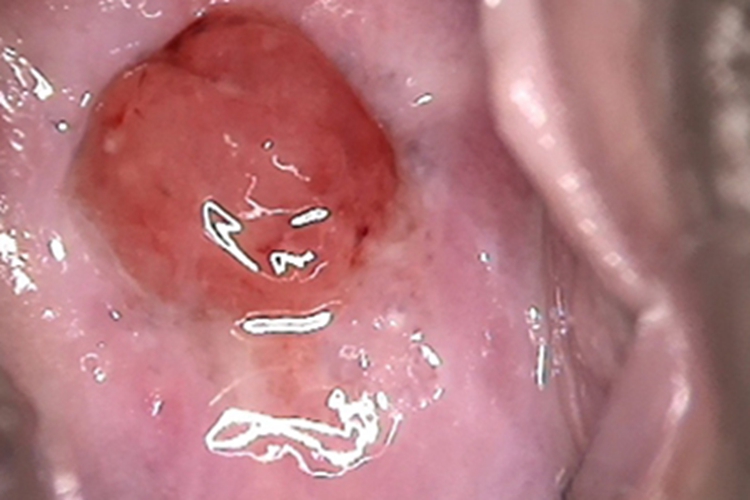

宫颈息肉检查可见患者宫颈口出现大肉球样增生,呈类圆形,颜色为鲜红色,质地比较柔软,表面光滑,有血液渗出,体积过大时会堵塞宫颈。